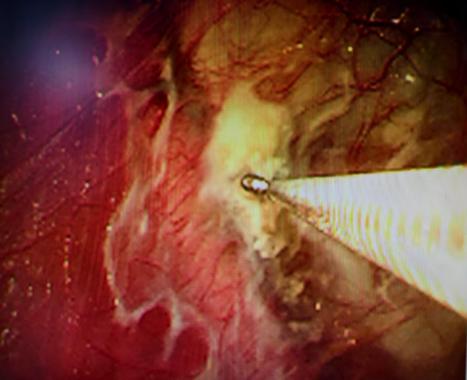

近期,国内知名呼吸介入专家陈愉教授联合澳博娱乐呼吸与危重症医学科团队,为李先生施行“胸腔镜下肺大疱探查术 + 胸腔闭式引流术”。手术中,陈愉教授运用单孔胸腔镜技术,仅在患者胸壁开了一个1cm的小切口。通过高清胸腔镜系统探查发现,患者胸腔内存在广泛粘连以及多发微小肺大疱,肺叶解剖结构异常,肺门血管直接暴露,经判断肺大疱腔已与胸腔贯通。

面对这一复杂状况,陈教授凭借丰富的经验果断调整手术方案。在确保安全的前提下,对可疑病灶进行了精准活检取样,随后精准置入胸腔引流管。术后即刻CT确认引流管位置良好,同时制定了严密的术后管理方案:每日监测引流量及肺复张情况,若引流量持续减少且肺大疱逐渐缩小,则按计划拨管;若肺大疱未明显缩小,则考虑拔除引流管后转外科进行胸膜剥离术。

(胸腔镜下可见胸腔粘连、多个微小肺大疱)